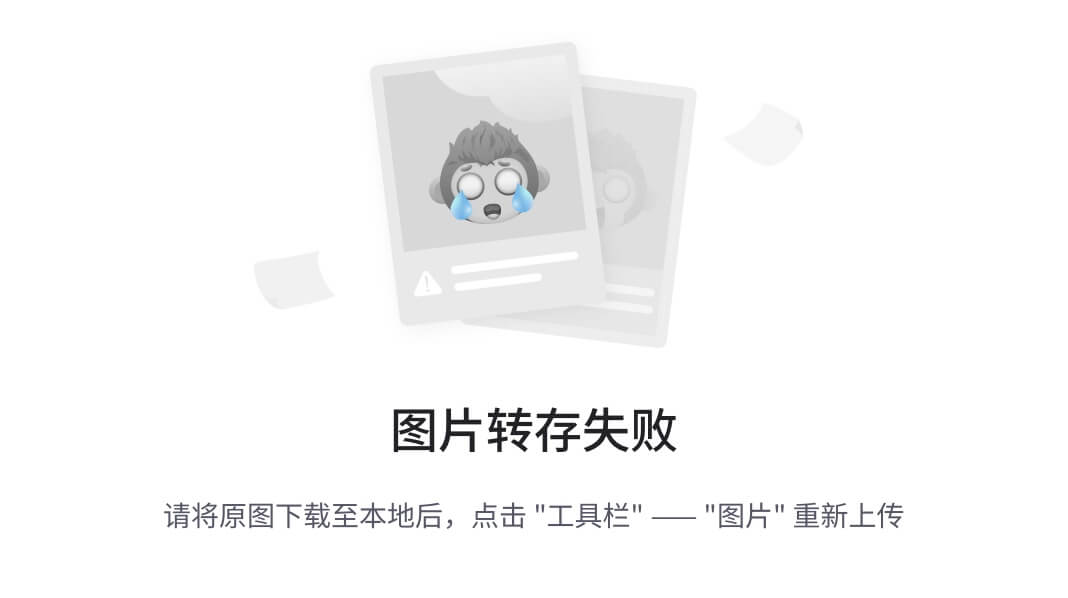

这意味着我们仍然专注于与第十一章相同的图 12.1 的同一部分。但现在我们正在努力使我们的分类模型工作良好而不是只是工作。本章重点讨论如何衡量、量化、表达,然后改进我们的模型执行工作的能力。

图 12.1 我们的端到端肺癌检测项目,重点放在本章的主题上:第 4 步,分类

虽然有点抽象,图 12.2 向我们展示了我们将如何处理那些广泛的主题。

让我们详细地走过本章的这张有些抽象的地图。我们将处理我们面临的问题,比如过度关注单一、狭窄的指标以及由此产生的行为在一般意义上是无用的。为了使本章的一些概念更具体化,我们将首先使用一个比喻来将我们的困境更具体化:在图 12.2 中,(1)看门狗和(2)鸟和窃贼。

图 12.2 我们将使用的比喻来修改衡量我们模型的指标,使其变得出色

之后,我们将开发一个图形语言来代表上一章实施中所需的核心概念:(3)比率:召回率和精确率。一旦我们将这些概念巩固下来,我们将涉及一些使用这些概念的数学,这将包括一种更健壮的评估我们模型性能的方式,并将其压缩为一个数字:(4)新指标:F1 分数。我们将实施这些新指标的公式,并查看在训练过程中每个时期这些结果值如何变化。最后,我们将对我们的LunaDataset实现进行一些急需的更改,以改善我们的训练结果:(5)平衡和(6)增强。然后我们将看看这些实验性的更改是否对我们的性能指标产生了预期的影响。

到本章结束时,我们训练的模型将表现得更好:(7)工作得很棒!虽然它还没有准备好立即投入临床使用,但它将能够产生明显优于随机的结果。这意味着我们已经有了可行的第 4 步实现,结节候选分类;一旦完成,我们可以开始考虑如何将第 2 步(分割)和第 3 步(分组)纳入项目中。